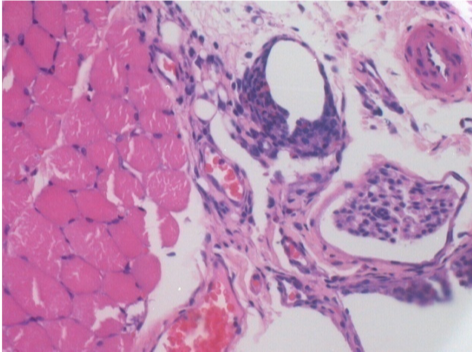

Через 1 місяць після ін'єкції Ендопілу 0,1 мл у правий претибіальний м'яз.

Те, що видно на знімках чорним кольором, не є некрозом, як можуть собі уявити деякі науковці!

Насправді, слід взяти до уваги 4 висновки